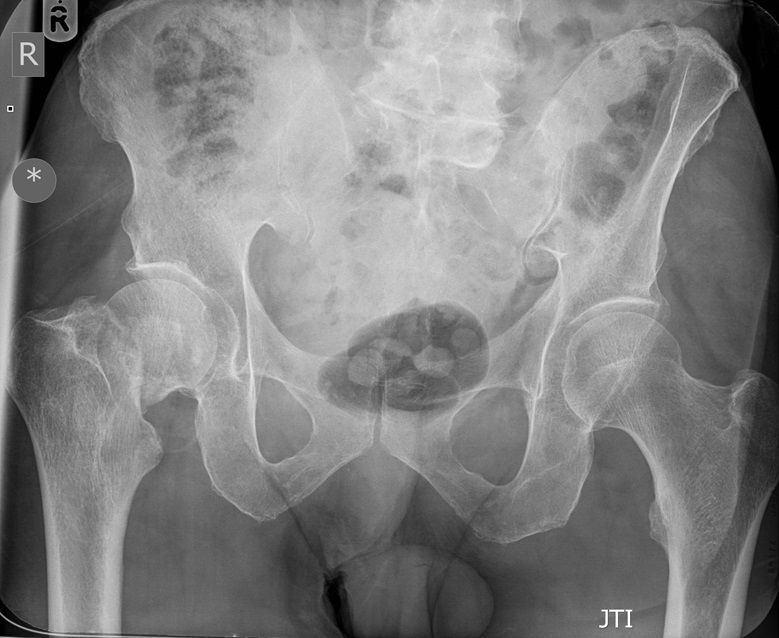

Question 1

Question

Which operation would you chose?

Answer

• THR

• Hemiarthroplasty